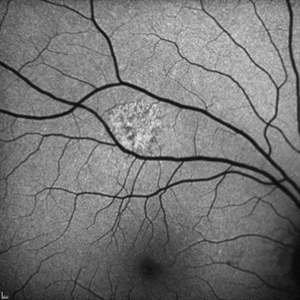

Unilateral Acute Idiopathic Maculopathy - Color Photo

Fundus photograph of a 32-year-old woman with several day history of inferior scotoma in the right eye. Vision in both eyes is 20/20. No vitreous cell in either eye. Has a history of hand, foot, and mouth disease 7-10 days prior to presentation. A diagnosis of unilateral acute idiopathic maculopathy was made.

Photographer: Kidron Robertson, Georgia Eye Institute of the Southeast, Savannah, GA

Condition/keywords: chorioretinal inflammations, Coxsackie, unilateral acute idiopathic maculopathy